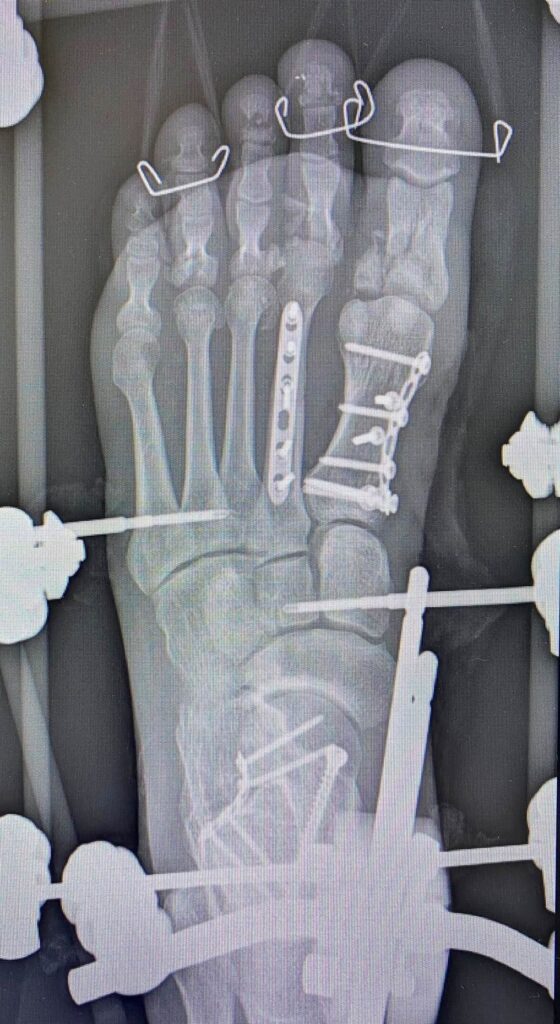

Petro Nikitin:

Наслідки скиду з дрона…

Хірургія стопи сьогодення (…це вам не Халюкси оперувати)

Дякую хірургу Степану Барабашу за чудову роботу